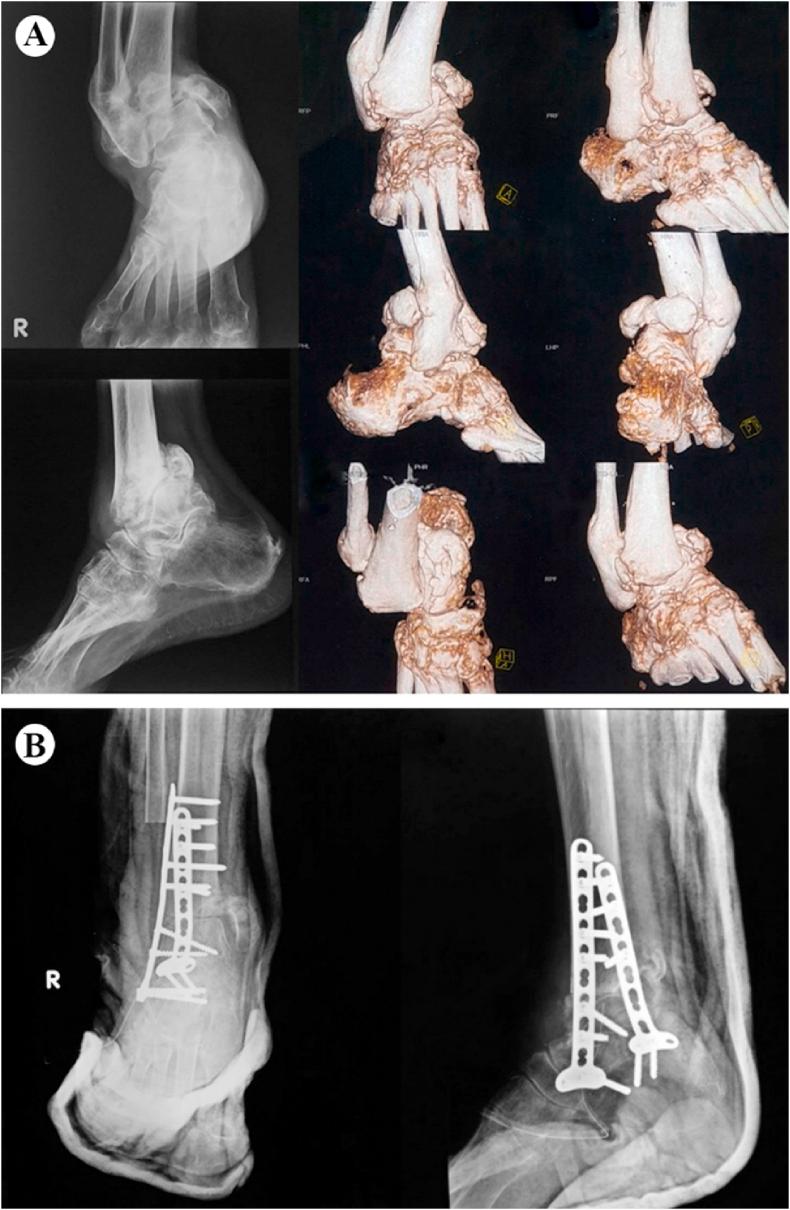

Ankle arthrodesis is one of the managements for a significantly unstable Charcot ankle. Some of the methods of internal fixation for ankle arthrodesis include the use of intramedullary nails, screws, and plates. Ankle arthrodesis using intramedullary nails has become more popular. However, studies evaluating the use of plate fixation, particularly double posterior lateral plating, are limited. We report the clinical and radiological outcomes of double posterior lateral plating ankle arthrodesis in three diabetic Charcot ankle patients.

Three patients, aged 73, 67, and 65 years old, complained of ankle pain and with a history of type 2 diabetes mellitus. The physical examination revealed swelling and erythema without a sign of active infection. The radiological examination showed ankle deformity, and the American Orthopaedic Foot & Ankle Society (AOFAS) Ankle-Hindfoot scores were 5, 10, and 0, respectively. All patients were diagnosed with a diabetic Charcot ankle and underwent ankle arthrodesis using double posterior lateral plating. Four months and six months follow up revealed talus union, improved ankle deformity, and improved AOFAS Ankle-Hindfoot scores to 70, 76, and 73, respectively.

Various methods of ankle arthrodesis are retrograde intramedullary nails, screws, and plates. In this report, we opt for plate fixation because it allows for stable internal fixation, adequate compression, high angular stability, and a lower irreversible deformation in osteoporotic bone.

踝关节融合术是治疗严重不稳定型夏科氏踝关节的方法之一。踝关节融合术的一些内固定方法包括使用髓内钉、螺钉和钢板。使用髓内钉进行踝关节融合术越来越受欢迎。然而,评估钢板固定,特别是双后外侧钢板固定的研究有限。我们报告了三例糖尿病性夏科氏踝关节患者采用双后外侧钢板固定踝关节融合术的临床和放射学结果。

三名患者,年龄分别为73岁、67岁和65岁,主诉踝关节疼痛,有2型糖尿病病史。体格检查发现肿胀和红斑,无活动性感染迹象。放射学检查显示踝关节畸形,美国矫形足踝协会(AOFAS)踝-后足评分分别为5分、10分和0分。所有患者均被诊断为糖尿病性夏科氏踝关节,并接受了双后外侧钢板固定的踝关节融合术。随访4个月和6个月时,距骨愈合,踝关节畸形改善,AOFAS踝-后足评分分别提高到70分、76分和73分。

踝关节融合术的各种方法包括逆行髓内钉、螺钉和钢板。在本报告中,我们选择钢板固定,因为它能提供稳定的内固定、足够的加压、高角度稳定性,并且在骨质疏松性骨中产生较低的不可逆变形。